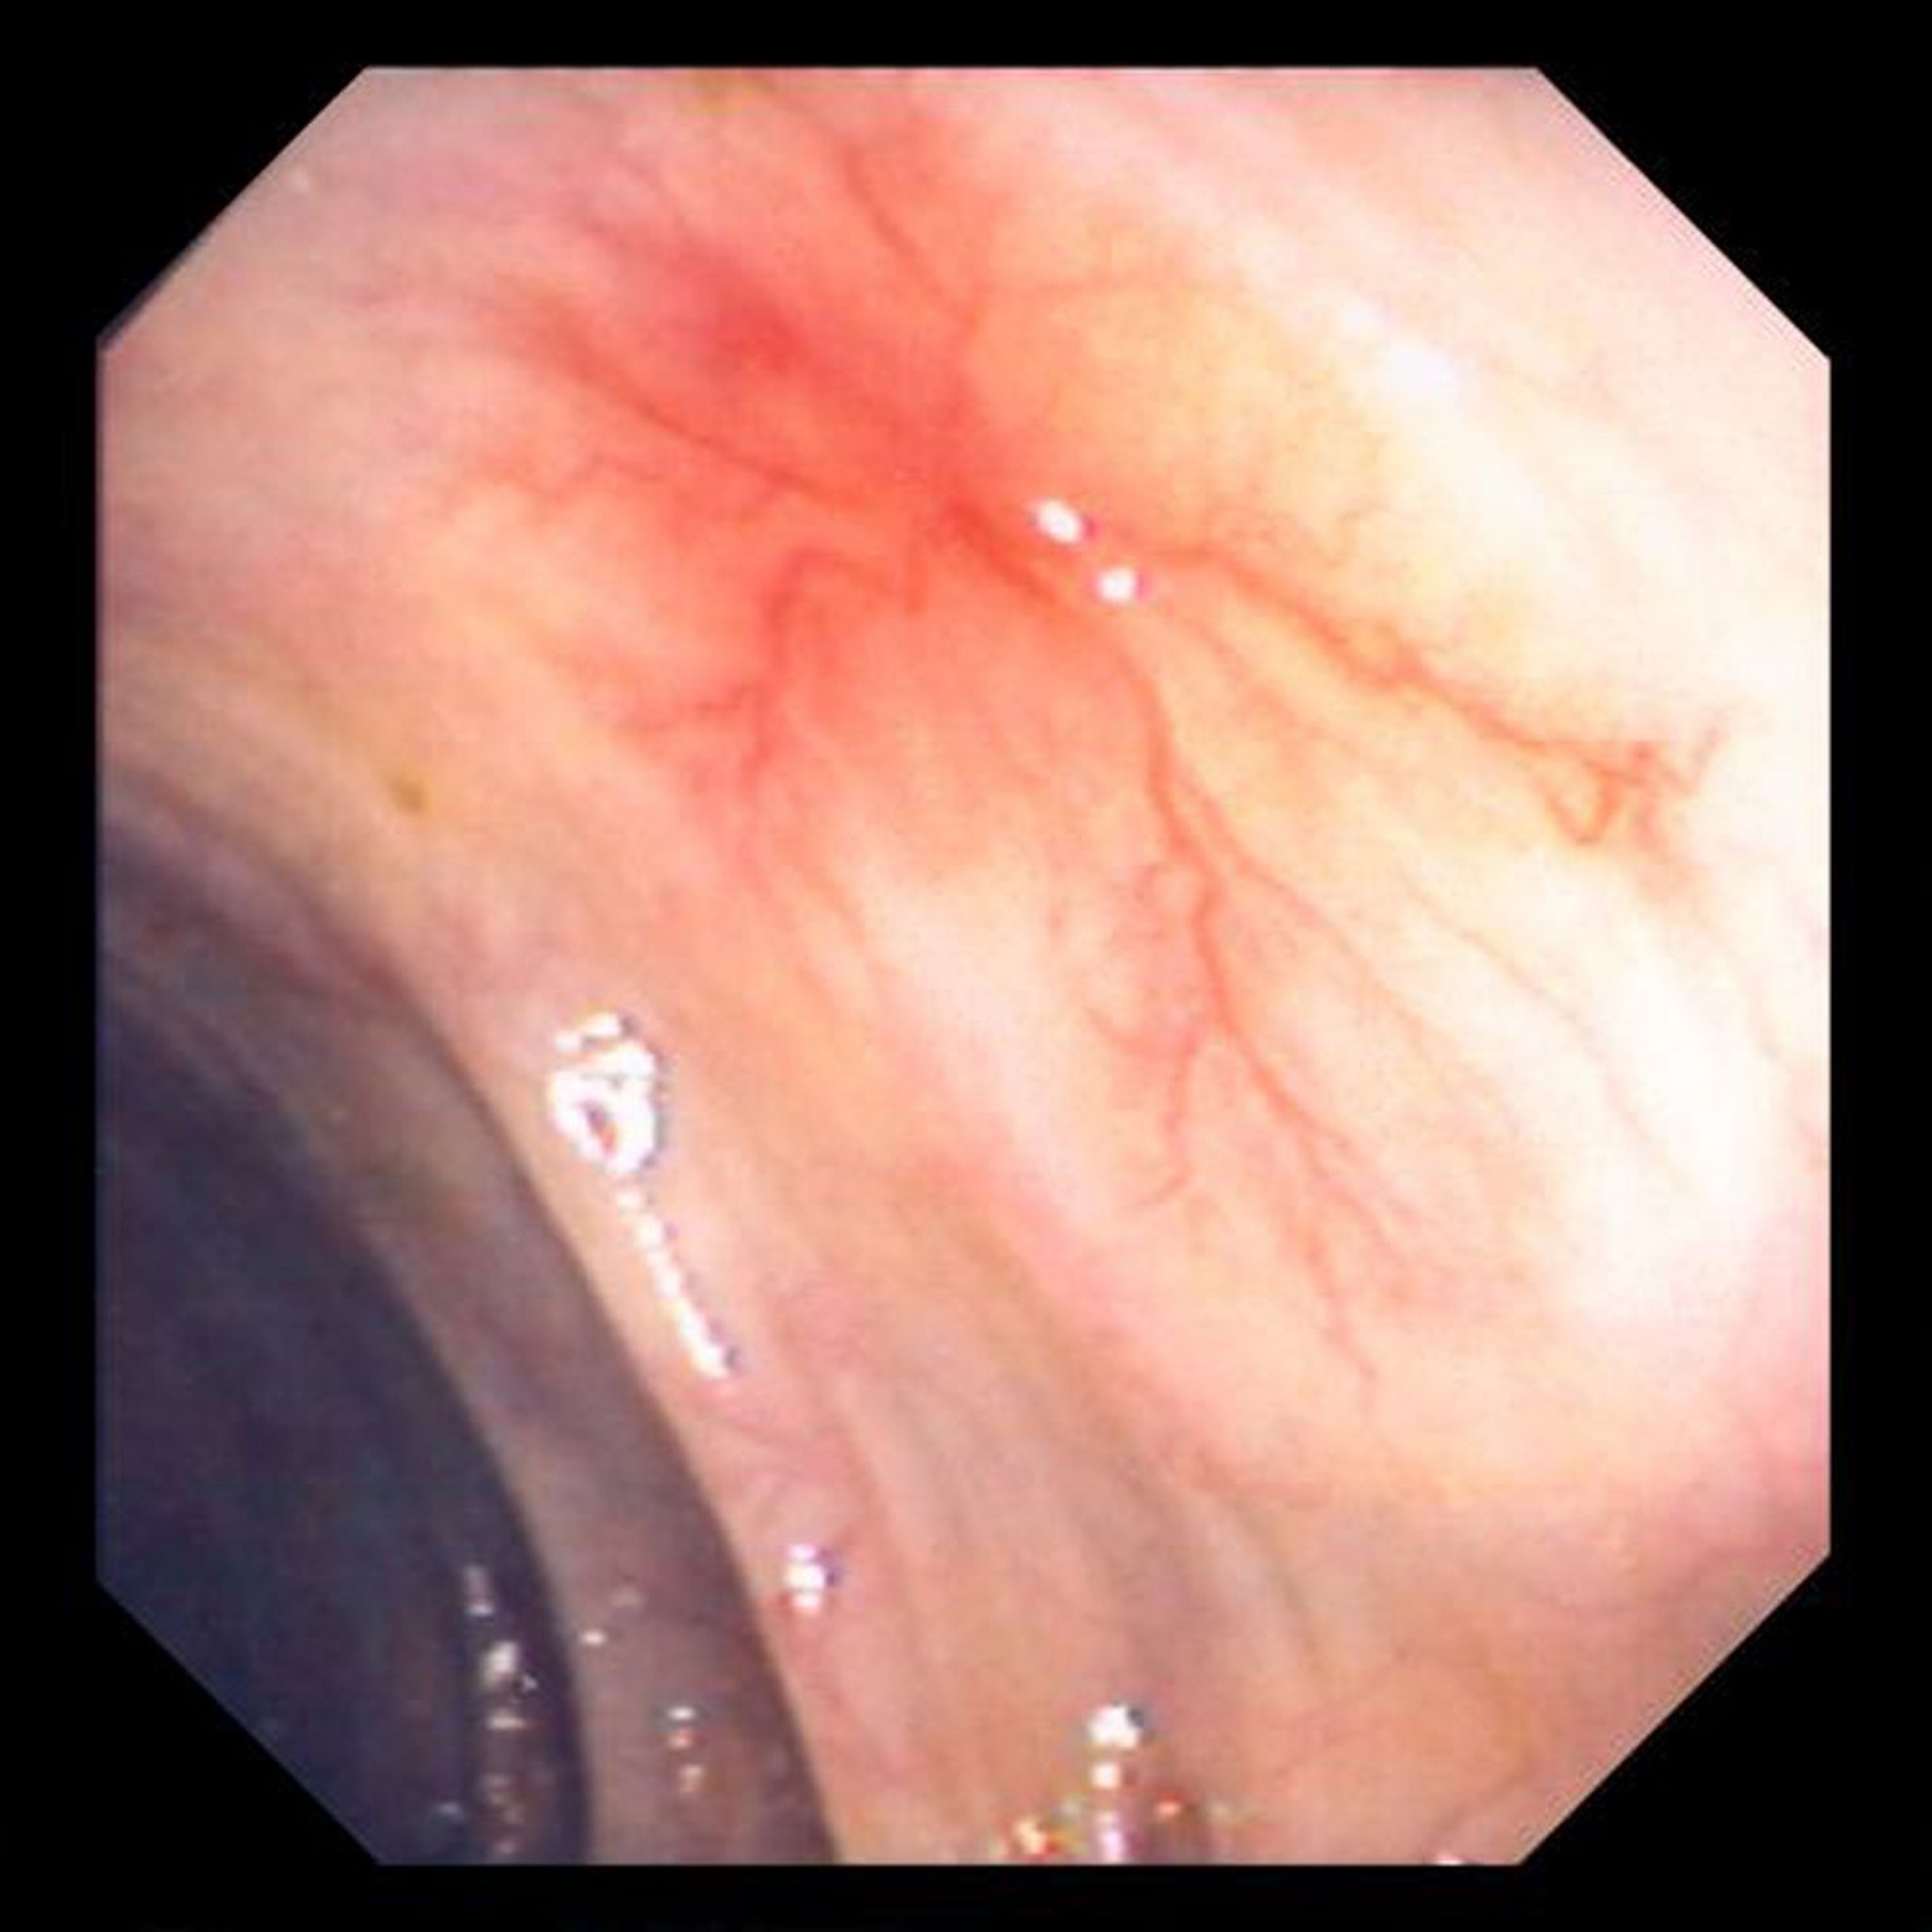

Ангіодисплазія

This photo shows vascular ectasia in the bowel wall.

Image provided by David M. Martin, MD.